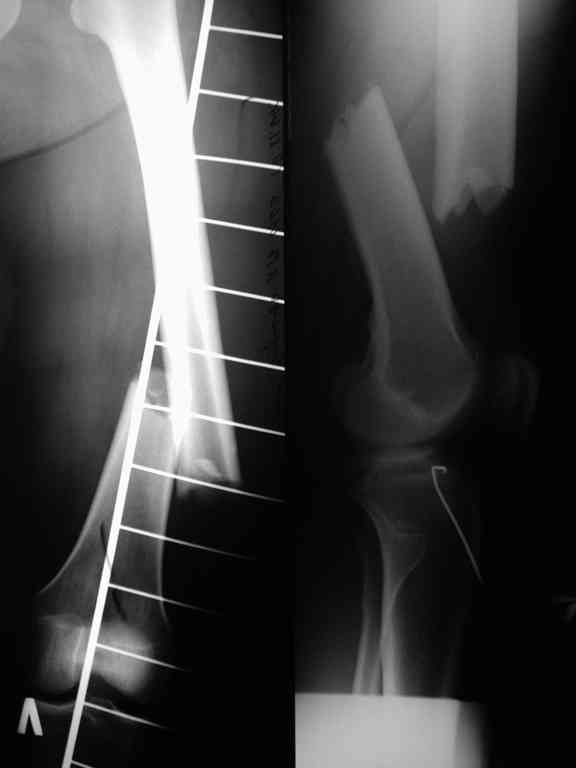

Соматически здорова. В ноябре 2004 года падение с высоты 12 м, перелом правой вертлужной впадины со смещением, неврит седалищного нерва, откр. перелом дистального отдела большеберцовой кости справа и закрытый перелом с/н/3 левого бедра. К нам поступила через 3 недели после травмы, был выполнен в 2 сессии сначала интрамедуллярный ретроградный остеосинтез бедра слева, затем остеосинтез вертлужной впадины и голеностопа справа. При остеосинтезе бедра пришлось немного приоткрыться в зоне перелома для репозиции и вообще операция затянулась часа на 2.5-3 (это один из наших первых интрамедуллярных синтезов). Через 4 месяца при нагрузке весом около 50 кг постепенно развилась варусная деформация бедра с искривлением стержня. Закрыто выпрямили под наркозом, динамизация гвоздя,но в сентябре 2005 г. согнулось бедро снова. Гвоздь удалили, остеосинтез пластиной, декортикация, пластика спонгиозой из метафиза б/берцовой кости. Динамика заживления вялая, но конструкция стояла неплохо (без признаков расшатывания), постепенно дали нагрузку - в марте 2006 года - перелом пластины - реостеосинтез пластиной, пластика гребнем подвздошной кости. На контролях (за август, т.е. 4 мес. после операции - прилагаю) динамика положительная, разрешена нагрузка до 50 кг. В начале этой недели без падения вновь появились боли в бедре - на Р-граммах - перелом пластины (снимки прилагаю). Фоном ко всему этому то, что и перелом вертлужки и дистального отдела б/б кости тоже не срастаются, хотя на голени уже дважды выполнялась костная пластика, на впадине - вторичное смещение, перелом части металлоконструкций. Исследовали гормональный фон - парат-гормон и прочие щитовидные в норме, месячные регулярно.Прошу совета по тактике дальнейшего лечения и выяснения причины тотального несращения всего сломанного.

В приложении рентгенограмма бедра за авгутст 2005 с согнутым гвоздем и первичные.